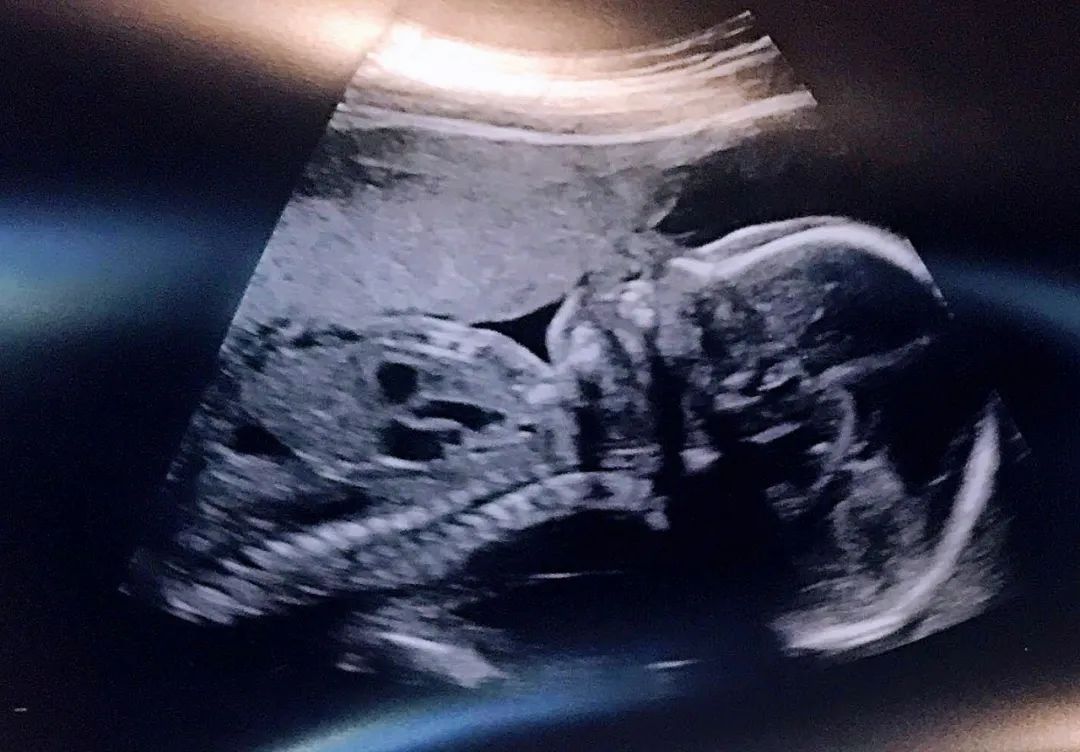

仿佛忽如其来的疾病还不足以让命运解气,脑瘤确诊六个月后,我的家庭医生在年常规体检时告知我已经怀孕 21 周,宝宝已经有白菜那么大了。因为脑瘤原因我没有正常的月事体征,再加上子宫后位和肿瘤药物副作用,我完全不显怀并且把每日的恶心、乏力当成是肿瘤药物的正常副作用。更要命的是,我所服用的肿瘤药物大概率致畸,所以对孕妇是绝对禁忌。当时的我完全不能相信自己会怀孕,而且居然都快孕五月了。我的医生曾经说过,脑垂体瘤会导致全身激素紊乱,不但无法受孕还会失去外围视觉。

生命以独特的方式告诉我它对未来自有安排。在做完了两次羊水穿刺,两次 3D 超声波,两次脑部核磁共振,和全套血检及基因排查后,我被告知宝宝奇迹般的没有发现任何物理形态上的畸形而我的脑瘤也没有肿胀迹象,然而宝宝以后是否会有因肿瘤药物原因导致的脑发育不全和认知障碍因缺少相关临床数据无法在产检时确认,所以我必须决定是否接受她以后会有认知障碍的风险。

昏暗的屋子里只有机器屏幕映出的微光,我听到一连串急促有力的陌生鼓点,我有些困惑,这听着不像正常人的心跳啊?也许是看出了我的疑惑,旁边的技师告诉我胎儿的心跳是成年人的两倍多。透过屏幕我可以清晰地看见她的每一根脊椎,十个手指头,和那颗拼命跳动、被四瓣心房包围着的小心脏。那细密紧促的心跳仿佛在告诉我:“妈妈,我想活,我想活”。